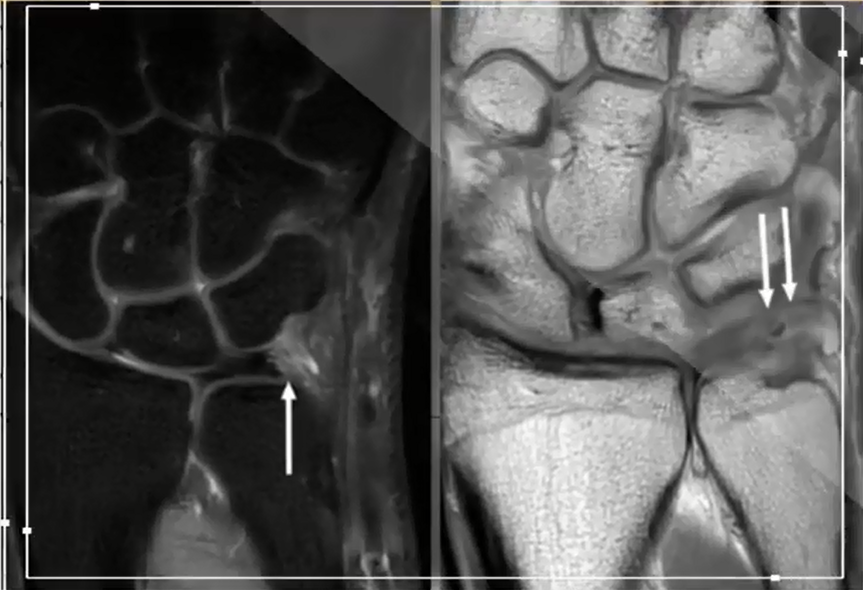

MR Imaging of the Triangular Fibrocartilage Complex Resonance Imaging Clinics

ABSTRACT. The triangular fibrocartilage complex (TFCC) of the carpus is a stabilizing structure of the wrist joint and more specifically the distal radioulnar joint (DRUJ), also acting as a load absorber for the ulnocarpal joint. Injuries to the TFCC are one of the most common causes of ulnar pain in the wrist joint.

Gross anatomy. The TFCC is located on the ulnar aspect of the wrist joint between the ulna and the lunate and triquetrum of the proximal carpal row. It has an elongated triangular shape with the apex pointing at the radius 5.. The complex is formed by multiple ligamentous and fibrocartilaginous components, including 1,2:. triangular fibrocartilage disc proper and triangular ligament